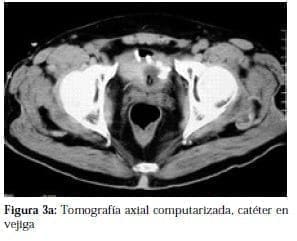

Una radiografía simple de abdomen (figura 1), cistografía (figura 2), las cuales mostraban la porción distal del catéter en la pelvis menor, así mismo se realizó urotac (figura 3a y b) que confirma la presencia del catéter en la vejiga.

Al paciente se le practica uretrocistoscopia que confirmo la presencia del catéter en vejiga (figuras 4a y b), bajo anestesia general se practica exploración abdominal, descartando presencia de catéter en esta cavidad, se realiza exploración del espacio prevesical evidenciando la presencia de catéter que se introducía a la vejiga por la parte media de la pared lateral izquierda (figura 5a).

La uropatia neurogénica que conlleva a vejigas atónicas o hipotónicas se asocia con diabetes de larga evolución. La placa de abdomen simple se puede considerar diagnostica, tanto en la posición antero posterior como oblicua, la porción distal del catéter entorchado, se encuentra en posición suprapúbica y sobre la silueta vesical y muy por debajo del repliegue peritoneal inferior, hallazgos que se confirmaron mediante Urotac y uretrocistoscopia, previos la corrección quirúrgica y reacomodación del catéter.